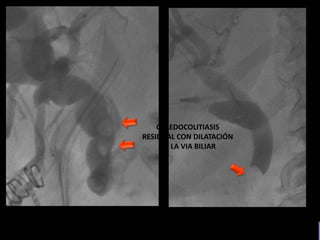

COLEDOCOLITIASIS

RESIDUAL CON DILATACIÓN

DE LA VIA BILIAR

RESIDUAL

• #18 Imagen por fluoroscopia evidencia imagen radiolucides de via biliar con dilatación de via intra y extra hepatica

• #19 Imagen por fluoroscopia evidencia imágenes radiopacas de bodes definidos en via biliar a nivel de colédoco A RELACIONAR CON COLEDOCOLITIASISS RESIDUAL